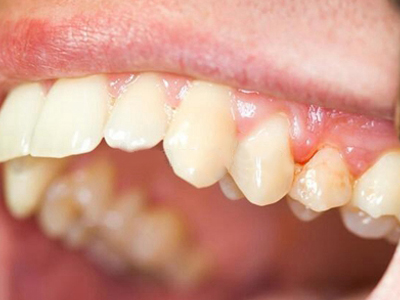

慢性龈炎又称边缘性龈炎或单纯性龈炎,主要表现为游离龈和龈乳头因炎性水肿,而变为鲜红或暗红色,龈缘变厚,龈乳头圆钝肥大。慢性龈炎的患病率高,治愈后仍可复发,部分患者可发展成为牙周炎。

慢性龈炎的病损部位一般局限于游离龈和龈乳头,以前牙区为主,尤其以下前牙区最为显著,患者常因刷牙或咬硬物时牙龈出血而就诊。游离龈和龈乳头颜色变为鲜红或暗红色,病变较重时炎性充血可波及附着龈。龈缘变厚,龈乳头圆钝肥大,可增生呈球状,覆盖牙面。牙龈松软脆弱,缺乏弹性。

龈缘附近牙面上堆积的牙菌斑是引起慢性龈炎的始动因子,其他如牙石、食物嵌塞、不良修复体等均可促使牙菌斑积聚,引发或加重牙龈炎症。